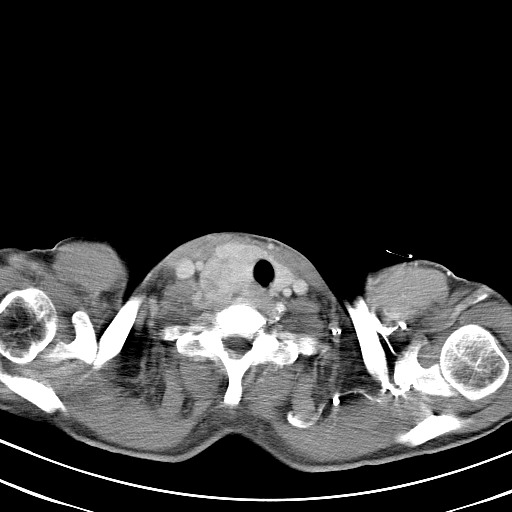

以下是引用汪涛同志在2007-8-2 0:40:00的发言:[br]病变虽然广泛,同时侵及双侧纵隔,但是无论左侧和右侧上下观察都是与右侧颈部甲状腺相延续的,而且强化幅度基本一致,又同时具有恶性病变病变的某些特征:肿块过大且密度不均,部分层面与正常纵隔结构分界不清,结合病史已有两年,考虑:胸内甲状腺肿恶变可能。[br]